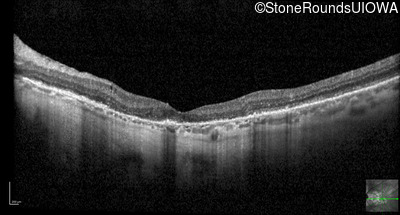

Optical Coherence Tomography - Left - 20/20 -2

Exemplar / OCT Stack

OCT Stack